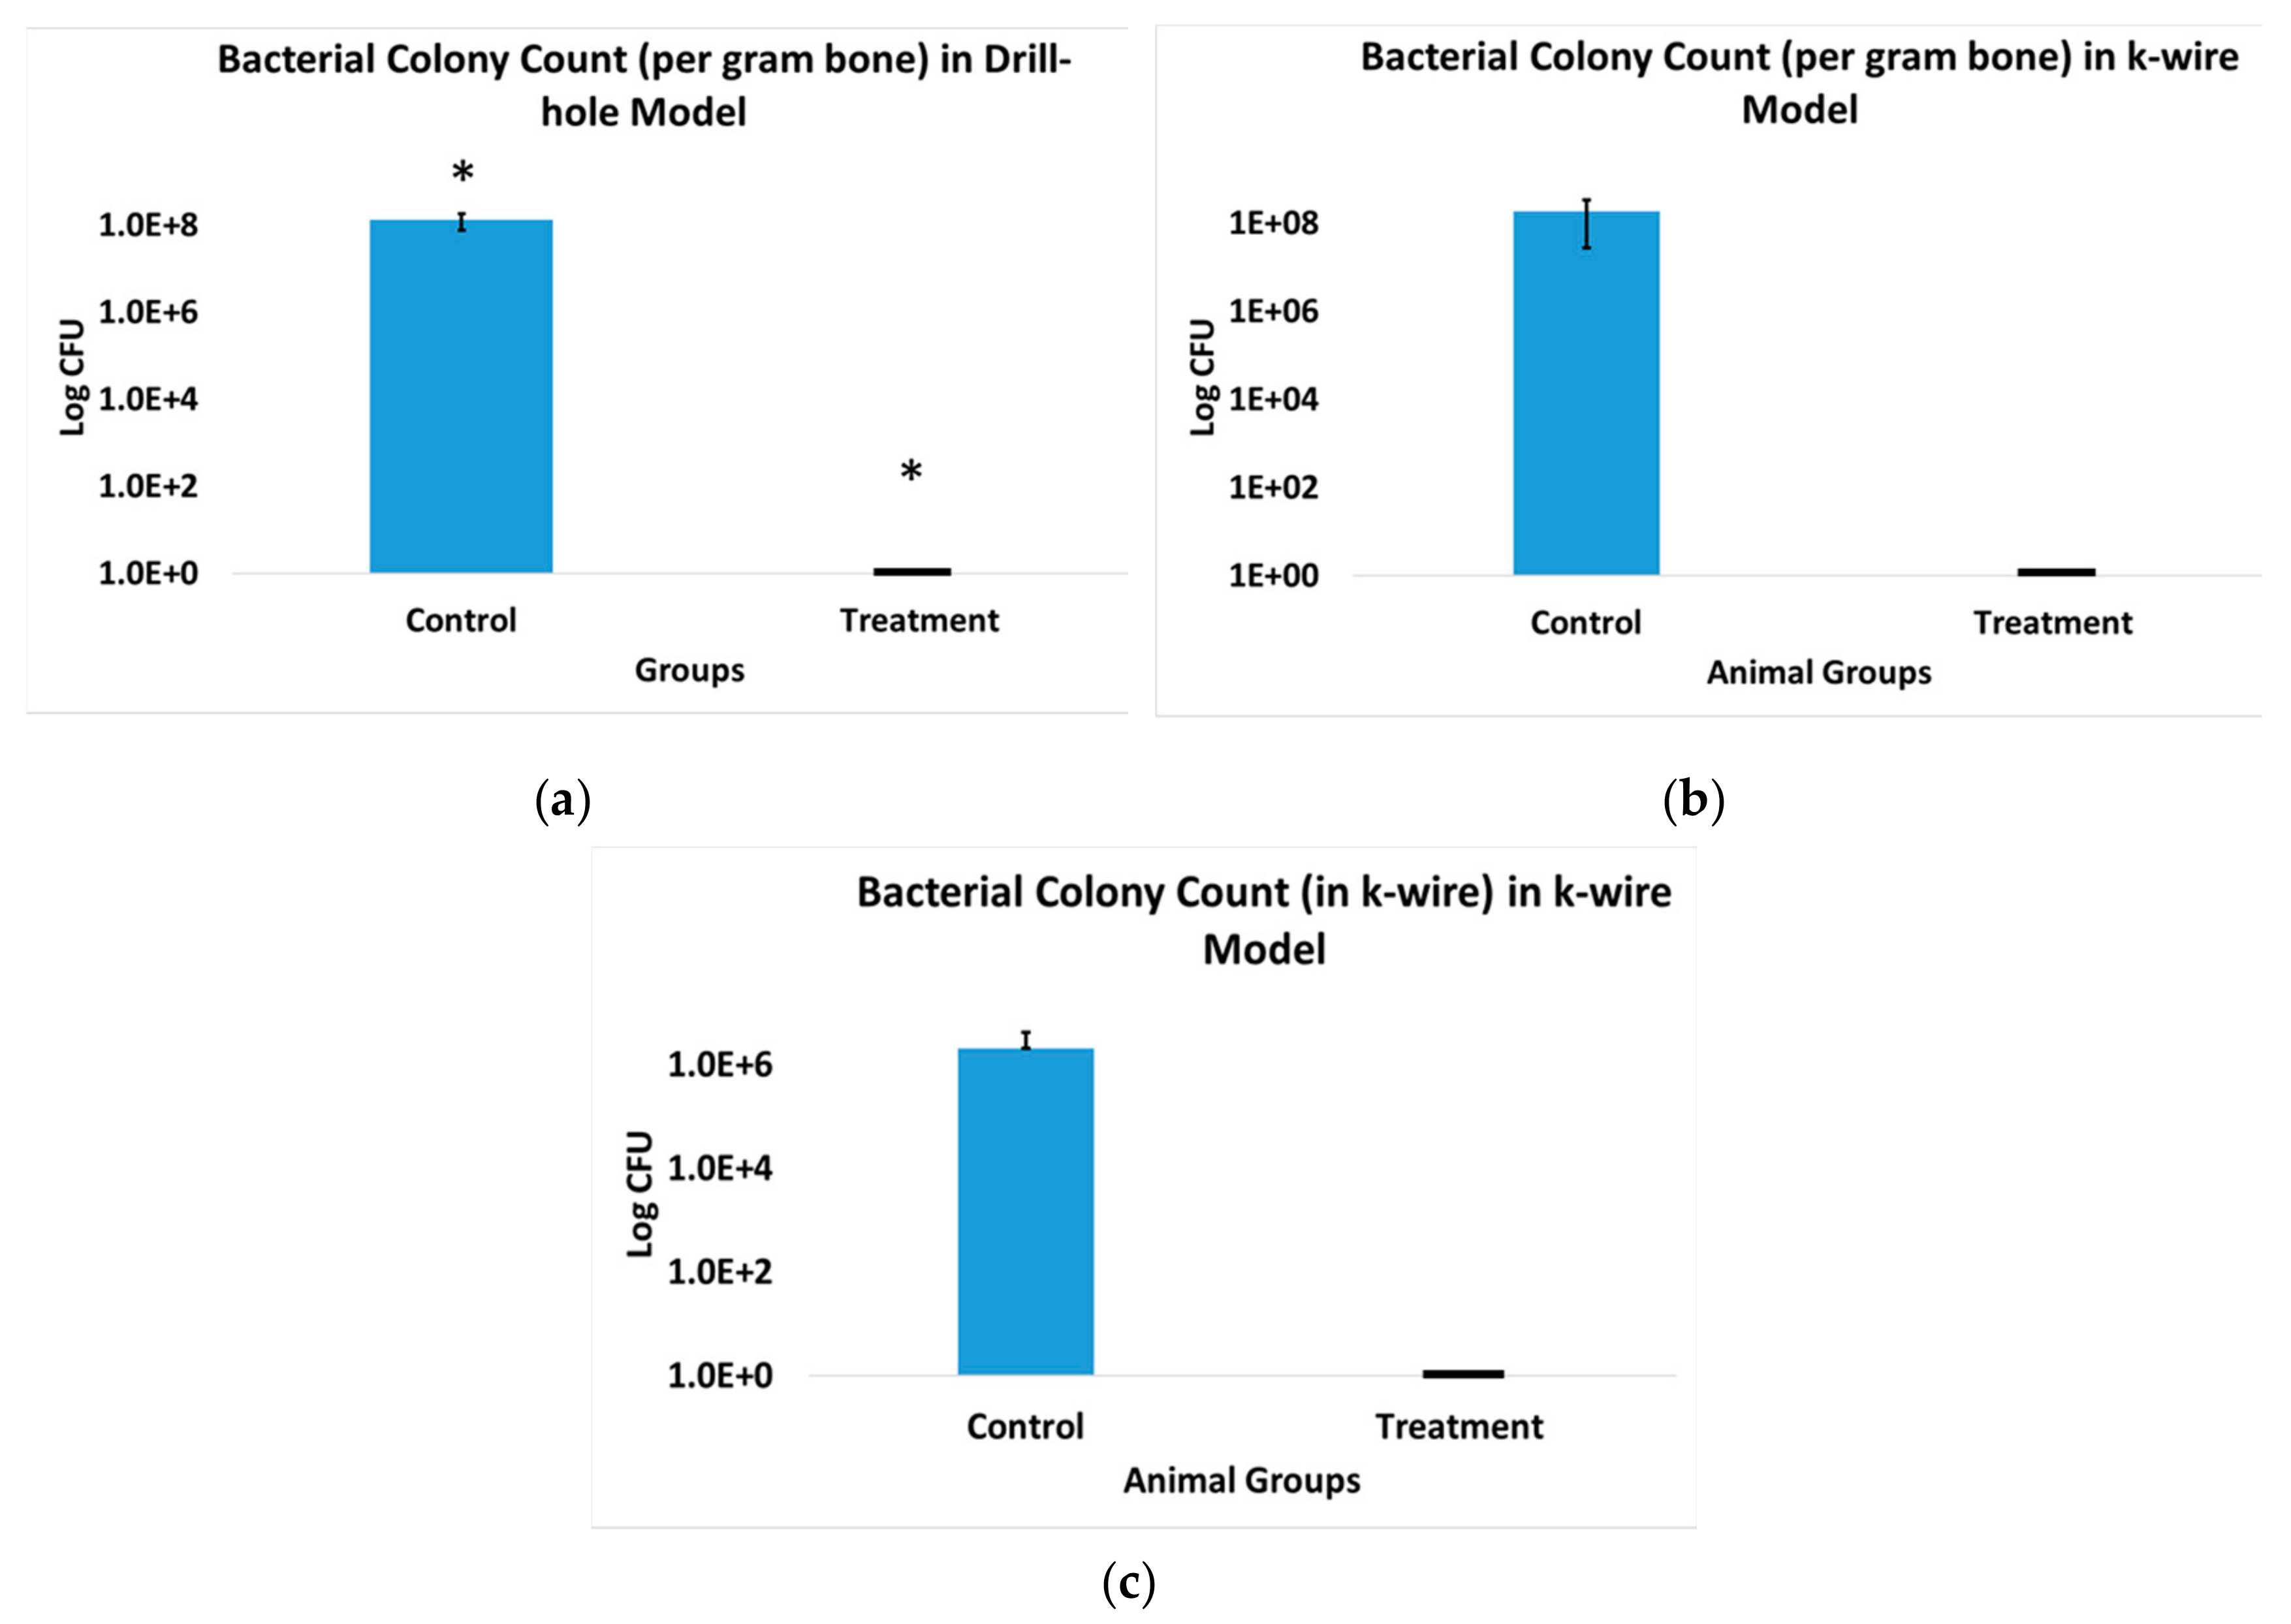

3.6. X-ray and Microcomputed Tomography (μ-CT)

3.7. Bone Volume of Newly Formed Bone